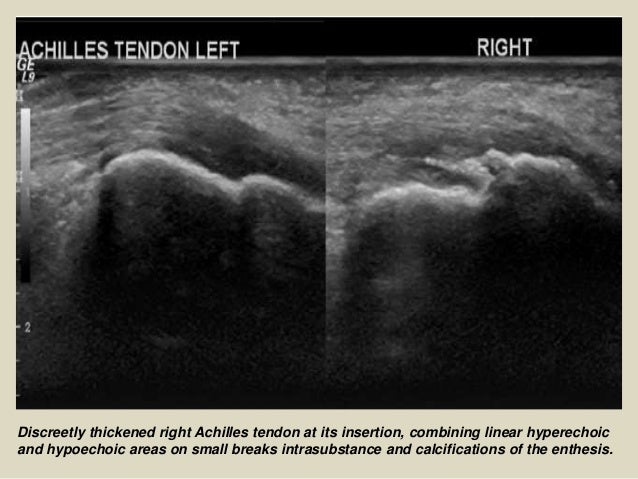

23. 23. Discreetly thickened right Achilles tendon at its insertion, combining linear hyperechoic and hypoechoic areas on small breaks intrasubstance and calcifications of the enthesis.

Discreetly thickened right Achilles tendon at its insertion, combining linear hyperechoic

and hypoechoic areas on small br...